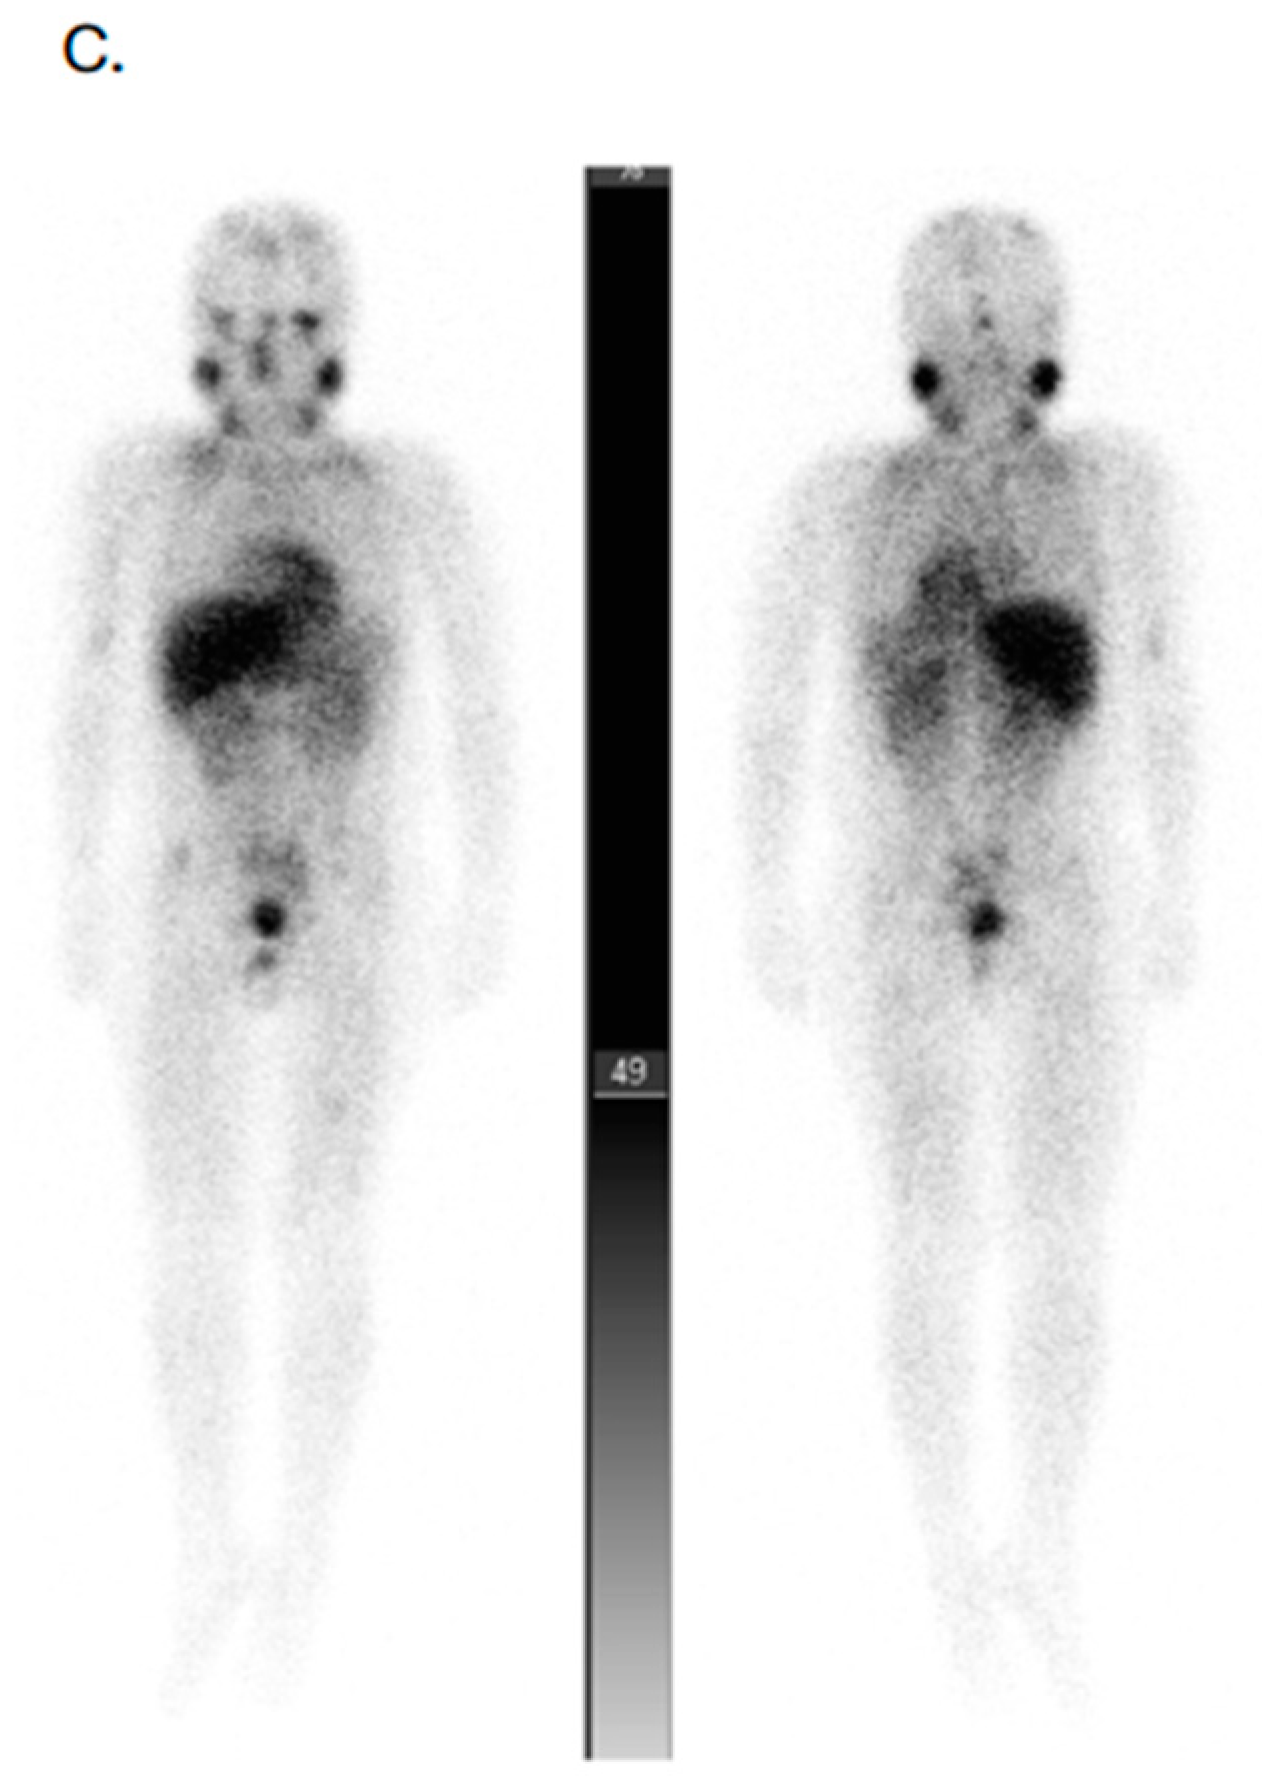

- Gains, J.E.; Aldridge, M.D.; Mattoli, M.V.; Bomanji, J.B.; Biassoni, L.; Shankar, A.; Gaze, M.N. 68Ga-DOTATATE and 123I-mIBG as imaging biomarkers of disease localisation in metastatic neuroblastoma: Implications for molecular radiotherapy. Nucl. Med. Commun. 2020, 41, 1169–1177. [Google Scholar] [CrossRef]

- Kong, G.; Hofman, M.S.; Murray, W.K.; Wilson, S.; Wood, P.; Downie, P.; Super, L.; Hogg, A.; Eu, P.; Hicks, R.J. Initial experience with gallium-68 DOTA-octreotate PET/CT and peptide receptor radionuclide therapy for pediatric patients with refractory metastatic neuroblastoma. J. Pediatr. Hematol. Oncol. 2016, 38, 87–96. [Google Scholar] [CrossRef]